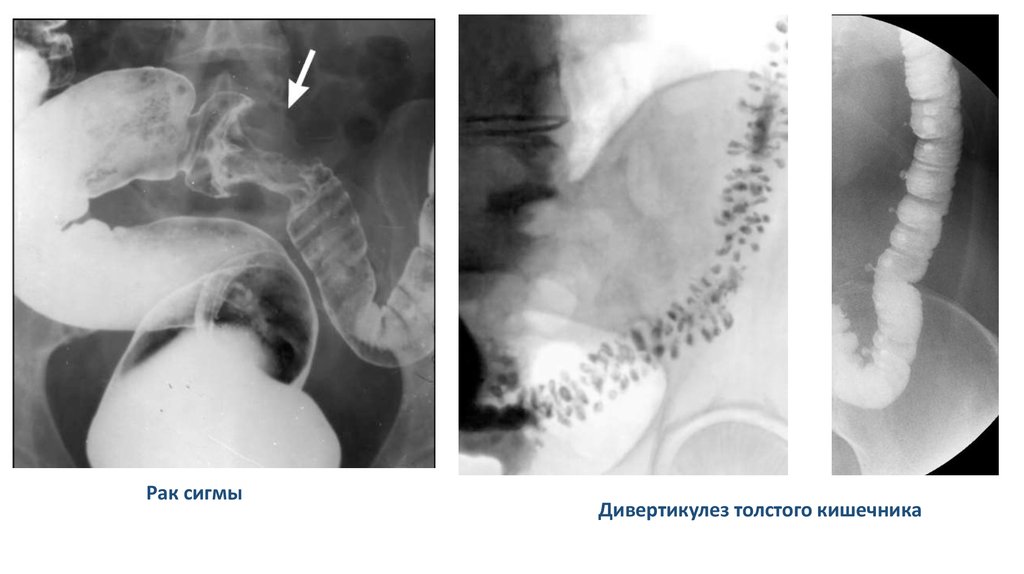

Рак сигмы

Дивертикулез толстого кишечника